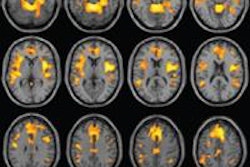

MRI shows a coronal view of the amygdala (red). Image courtesy of Rosalind Franklin University of Medicine and Science.The results showed that the amygdala was approximately 10% larger in male brains; however, the difference was comparable to males' larger body size, including the 11% to 12% larger volume of their brains overall. Among studies that adjusted for overall brain size, the volume difference was less than 0.1% in the right amygdala and 2.5% in the left amygdala, both of which were not statistically significant.